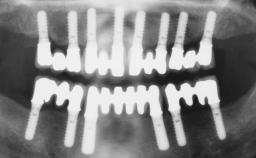

Immediate Loading of Six Implants in the Maxilla and Final Restoration with a Full-Arch CAD/CAM Zirconia FDP

A 63-year-old male patient was referred for a consultation and treatment of partial edentulism in the maxilla. The patient presented with residual anterior teeth and declined a partial removable prosthesis. He reported that the maxillary posterior teeth had been extracted due to mobility and periodontal disease two months before the consultation. The patient’s chief complaint was that his residual maxillary teeth were mobile and that he was unable to chew. The patient’s desire was a stable and comfortable fixed maxillary rehabilitation. The patient was a light smoker (fewer than 10 cigarettes/ day), and his medical history was without significant findings. He was not on any regular medication at the time of consultation. The extraoral examination revealed a normal physiognomy with a correct distribution of the facial thirds. The patient presented a low lip line, and the transition line between teeth and soft tissues was not exposed during a forced smile.

# of Implants 6

Bone Augmentation Horizontal|Simultaneous